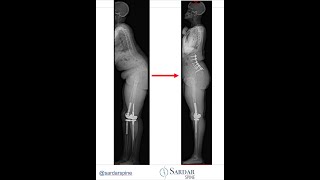

Case of a person with severe sagittal mal alignment of the spine and inability to stand up straight

Zeeshan Sardar, MD - Spine and Scoliosis Surgeon

Case of a person with severe sagittal mal alignment of the spine with inability to stand straight